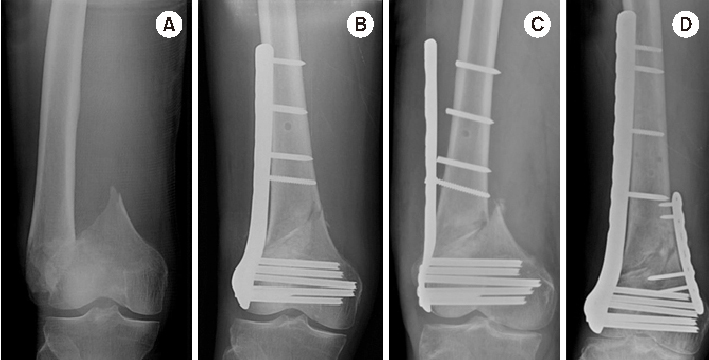

Fig. 4

(A) Distal femur fracture in a 70-year-old male. (B) Postoperative anteroposterior radiograph after minimally invasive locked plating. (C) Fixation failure along with broken locking screws two months after surgery. (D) Anteroposterior radiograph seven months after double plating showing bony union.